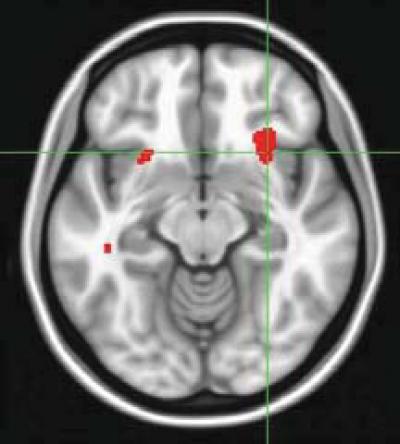

Pre-treatment scans of brain activity predicted whether depressed patients would best achieve remission with an antidepressant medication or psychotherapy, in a study funded by the National Institutes of Health.

Mayberg's team hoped to identify a biomarker that could predict which type of treatment a patient would benefit from based on the state of his or her brain. Using a positron emission tomography (PET) scanner, they imaged pre-treatment resting brain activity in 63 depressed patients. PET pinpoints what parts of the brain are active at any given moment by tracing the destinations of a radioactively-tagged form of glucose, the sugar that fuels its metabolism.

Activity in one specific brain area emerged as a pivotal predictor of outcomes from two standard forms of depression treatment: cognitive behavior therapy (CBT) or escitalopram, a serotonin specific reuptake inhibitor (SSRI) antidepressant. If a patient's pre-treatment resting brain activity was low in the front part of an area called the insula, on the right side of the brain, it signaled a significantly higher likelihood of remission with CBT and a poor response to escitalopram. Conversely, hyperactivity in the insula predicted remission with escitalopram and a poor response to CBT.

Among several sites of brain activity related to outcome, activity in the anterior insula best predicted response and non-response to both treatments. The anterior insula is known to be important in regulating emotional states, self-awareness, decision-making and other thinking tasks. Changes in insula activity have been observed in studies of various depression treatments, including medication, mindfulness training, vagal nerve stimulation and deep brain stimulation.